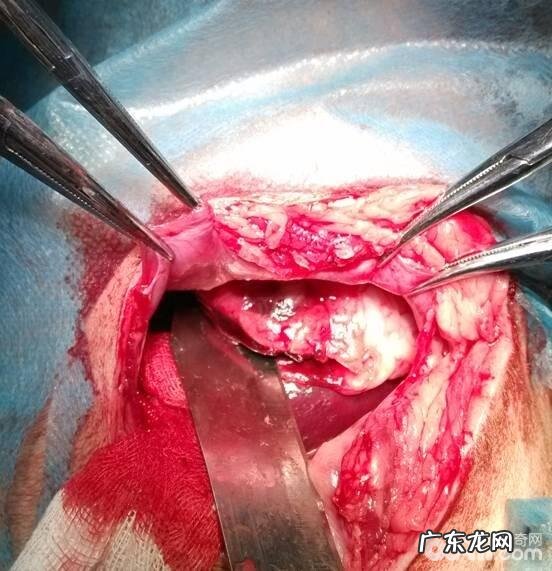

经查验后 , 麻醉剂备皮后 , 由伤口部位割开肌肤探察刀刺进部位 , 见到刀深层次胃里 , 胃里有创口 。

再次探察 , 发觉伤口刺进肝脏 , 将刀头轻轻地取下后 , 旋转肝脏 , 发觉肝脏上边的创口 , 遂决策开展脾脏切除术 。